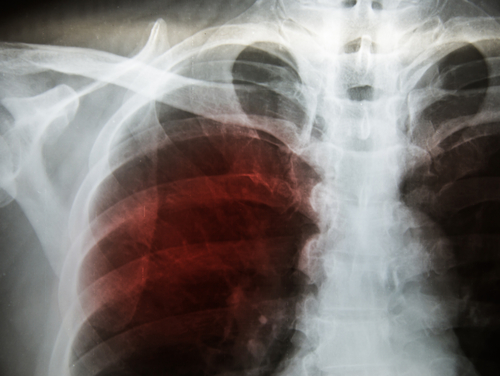

According to a recent study, researchers are training artificial intelligence models to identify Tuberculosis (TB) on chest X-rays, which may help screening and evaluation efforts in TB-prevalent areas with limited access to radiologists.

The study was published in journal Radiology. According to the World Health Organization, TB is one of the top ten causes of death worldwide. In 2016, approximately 10.4 million people fell ill from TB, resulting in 1.8 million deaths. TB can be identified on chest imaging, however, TB-prevalent areas typically lack the radiology interpretation expertise needed to screen and diagnose the disease.